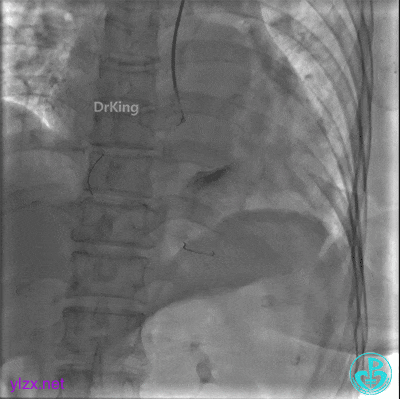

既往有脑梗死病史4年、高血压病史4年,口服降压药及血压控制情况不详;2年前于院外行股静脉滤网置入治疗。

急诊冠脉造影

PL分支开口闭塞,PD分支血流3级,开口处可见血栓。